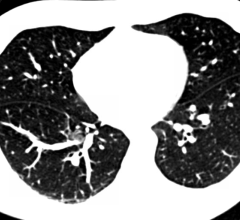

Contributing Editor Greg Freiherr offers an overview of computed tomography (CT) advances at the Radiological Society of North America (RSNA) 2015. The video includes Freiherr during his booth tours with some of the key vendors who were featuring new technology.

Computed Tomography (CT)

May 12, 2014 — The American College of Radiology (ACR) is accepting applications for its new ACR Lung Cancer Screening…